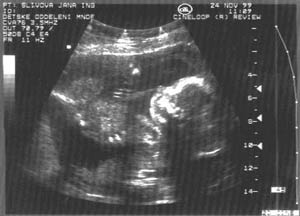

10. týden: dvojvaječná dvojčata

10.týden